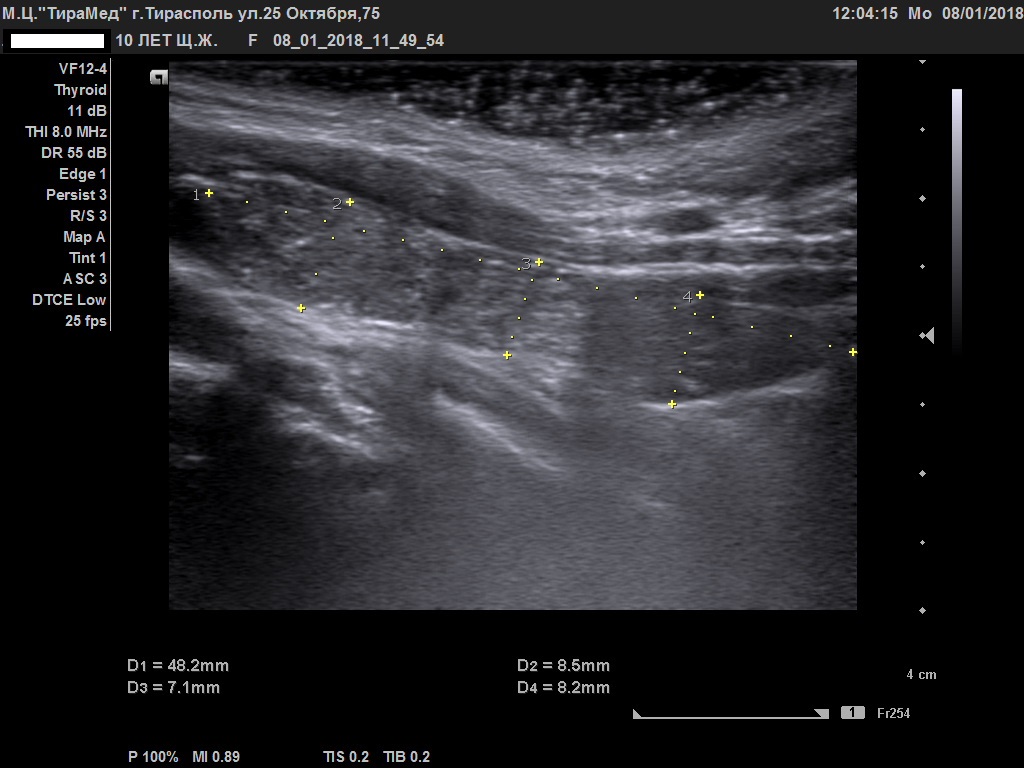

Тимомегалия: что это такое и как проявляется

Раздел: Фотоальбом решений